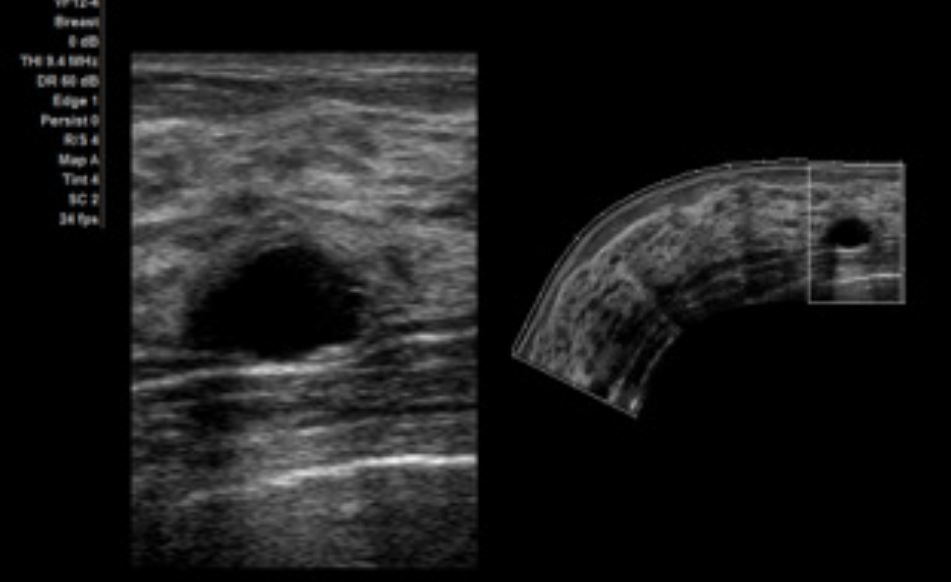

SieScape 全景成像选件

- 适用于线阵和凸阵探头

- 当扫描深度低于目标扫描区域半径时,可以创建长度达60 cm、角度达 360°的 SieScape 影像

- 可逐帧复查 SieScape 影像中单个数据帧的电影显示